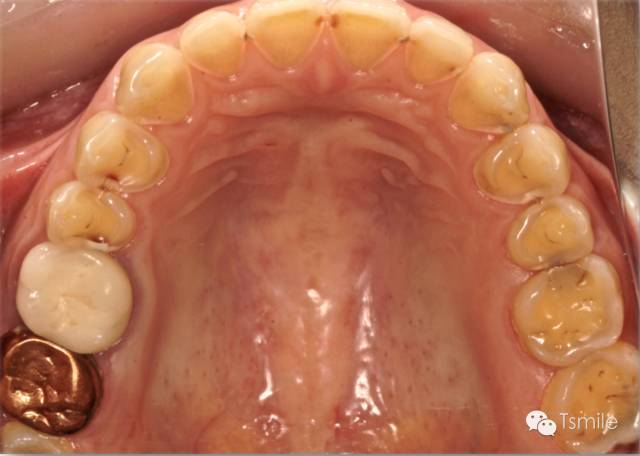

胃食管返流病,英文名Gastroesophageal Reflux Disease,簡(jiǎn)稱GERD,是由于消化系統(tǒng)疾病導(dǎo)致胃液返流至口腔內(nèi),胃液接觸牙齒表面,胃酸對(duì)牙齒硬組織造成嚴(yán)重酸蝕脫礦。胃食管返流病導(dǎo)致的牙列重度磨耗主要發(fā)生于上頜牙齒的舌面以及下頜磨牙的頜面。胃食管返流病患者在夜間睡眠時(shí)胃液返流導(dǎo)致的牙齒酸蝕脫礦最為嚴(yán)重,由于患者的睡姿體位不同,因而造成牙齒酸蝕脫礦的部位和程度在牙弓左右兩側(cè)并不對(duì)稱。

圖5: 胃食管返流病導(dǎo)致的牙列重度磨耗